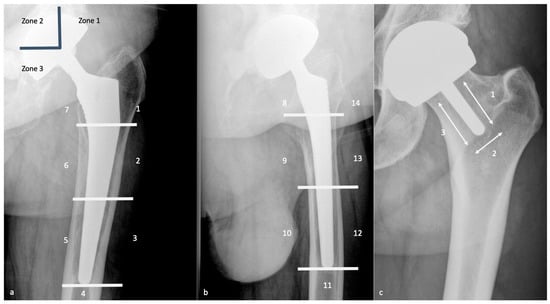

| Measurement | Normal Value | Consequences of Mispositioning |

|---|---|---|

| Leg Length | < 0.5–1 cm of differences between both sides | Increased discrepancy: gluteal and iliopsoas muscles affection |

| Acetabular side | ||

| Frontal acetabular inclination | 40 ± 15° | - Decreased: hip abduction limitation |

| - Increased: dislocation risk | ||

| Sagittal acetabular inclination | 35–40 ± 10° in standing position | - Increased: posterior impingement, anterior dislocation |

| 52 ± 11° in sitting position | - Decreased: anterior impingement between the cup and the neck, posterior dislocation | |

| Acetabular anteversion | 5–25° | - Lack of anteversion or retroversion: posterior dislocation, iliopsoas impingement |

| - Excessive anteversion: anterior dislocation | ||

| Acetabular center of rotation position | Similar to the contralateral hip | Lateralized: dislocation risk |

| Femoral Offset | 41–44 mm (or similar to contralateral hip) | - Decreased: limping, mobility limitation, and dislocation by gluteal muscles weakness |

| - Increased: gluteal muscles pain and polyethylene wear | ||

| Femoral side | ||

| Femoral Stem position | Neutral or slight valgus | Periprosthetic fracture and stress reaction in case of varus |

| Femoral Neck Anteversion | 10–15° | - Increased: anterior dislocation and ischio-femoral impingement |

| - Decreased: posterior dislocation | ||

| Femoral Head | Centered or slightly inferiorly located | - Particle disease if located upwards (wear) |